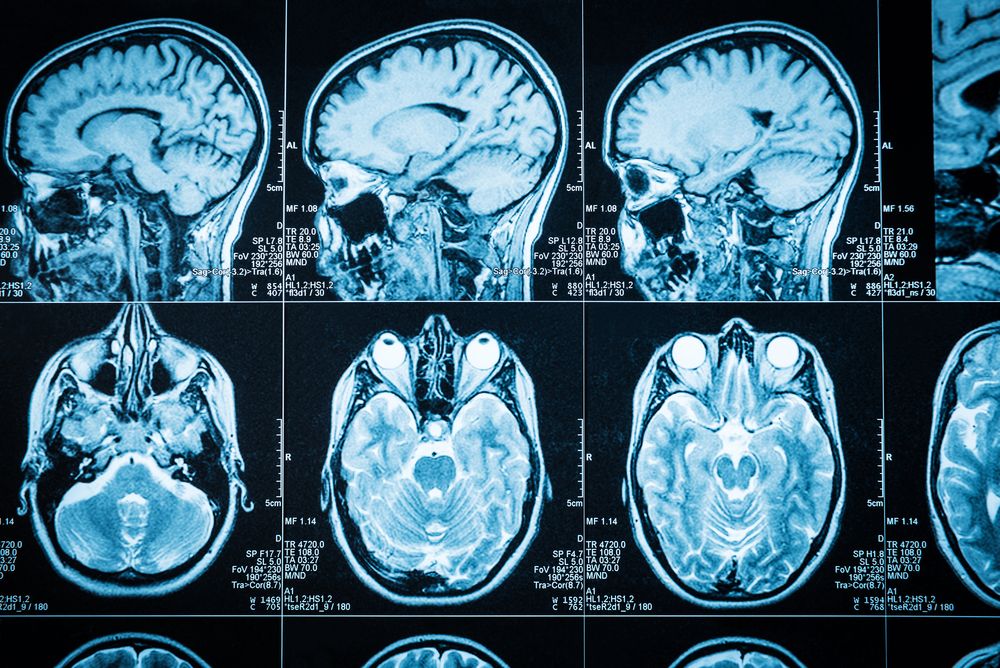

Computed tomography (CT) scan pada kepala adalah metode diagnosis menggunakan prosedur pencitraan (imaging) dengan bantuan X-ray khusus untuk menghasilkan gambar otak secara horizontal.

CT scan jenis ini dapat memberikan informasi yang lebih detail mengenai jaringan dan struktur otak daripada metode diagnosis lainnya. Alhasil, dokter akan lebih mudah mengetahui jika ada cedera atau masalah kesehatan otak.

Saat menjalani pemeriksaan dengan CT scan kepala, sinar X-ray akan bergerak mengelilingi tubuh Anda. Tujuannya, untuk mengambil gambar otak dari berbagai sudut pandang.

Kemudian, informasi yang berhasil didapatkan akan dikirim ke komputer untuk menerjemahkan data dari X-ray dan menampilkan versi dua dimensinya pada layar monitor.